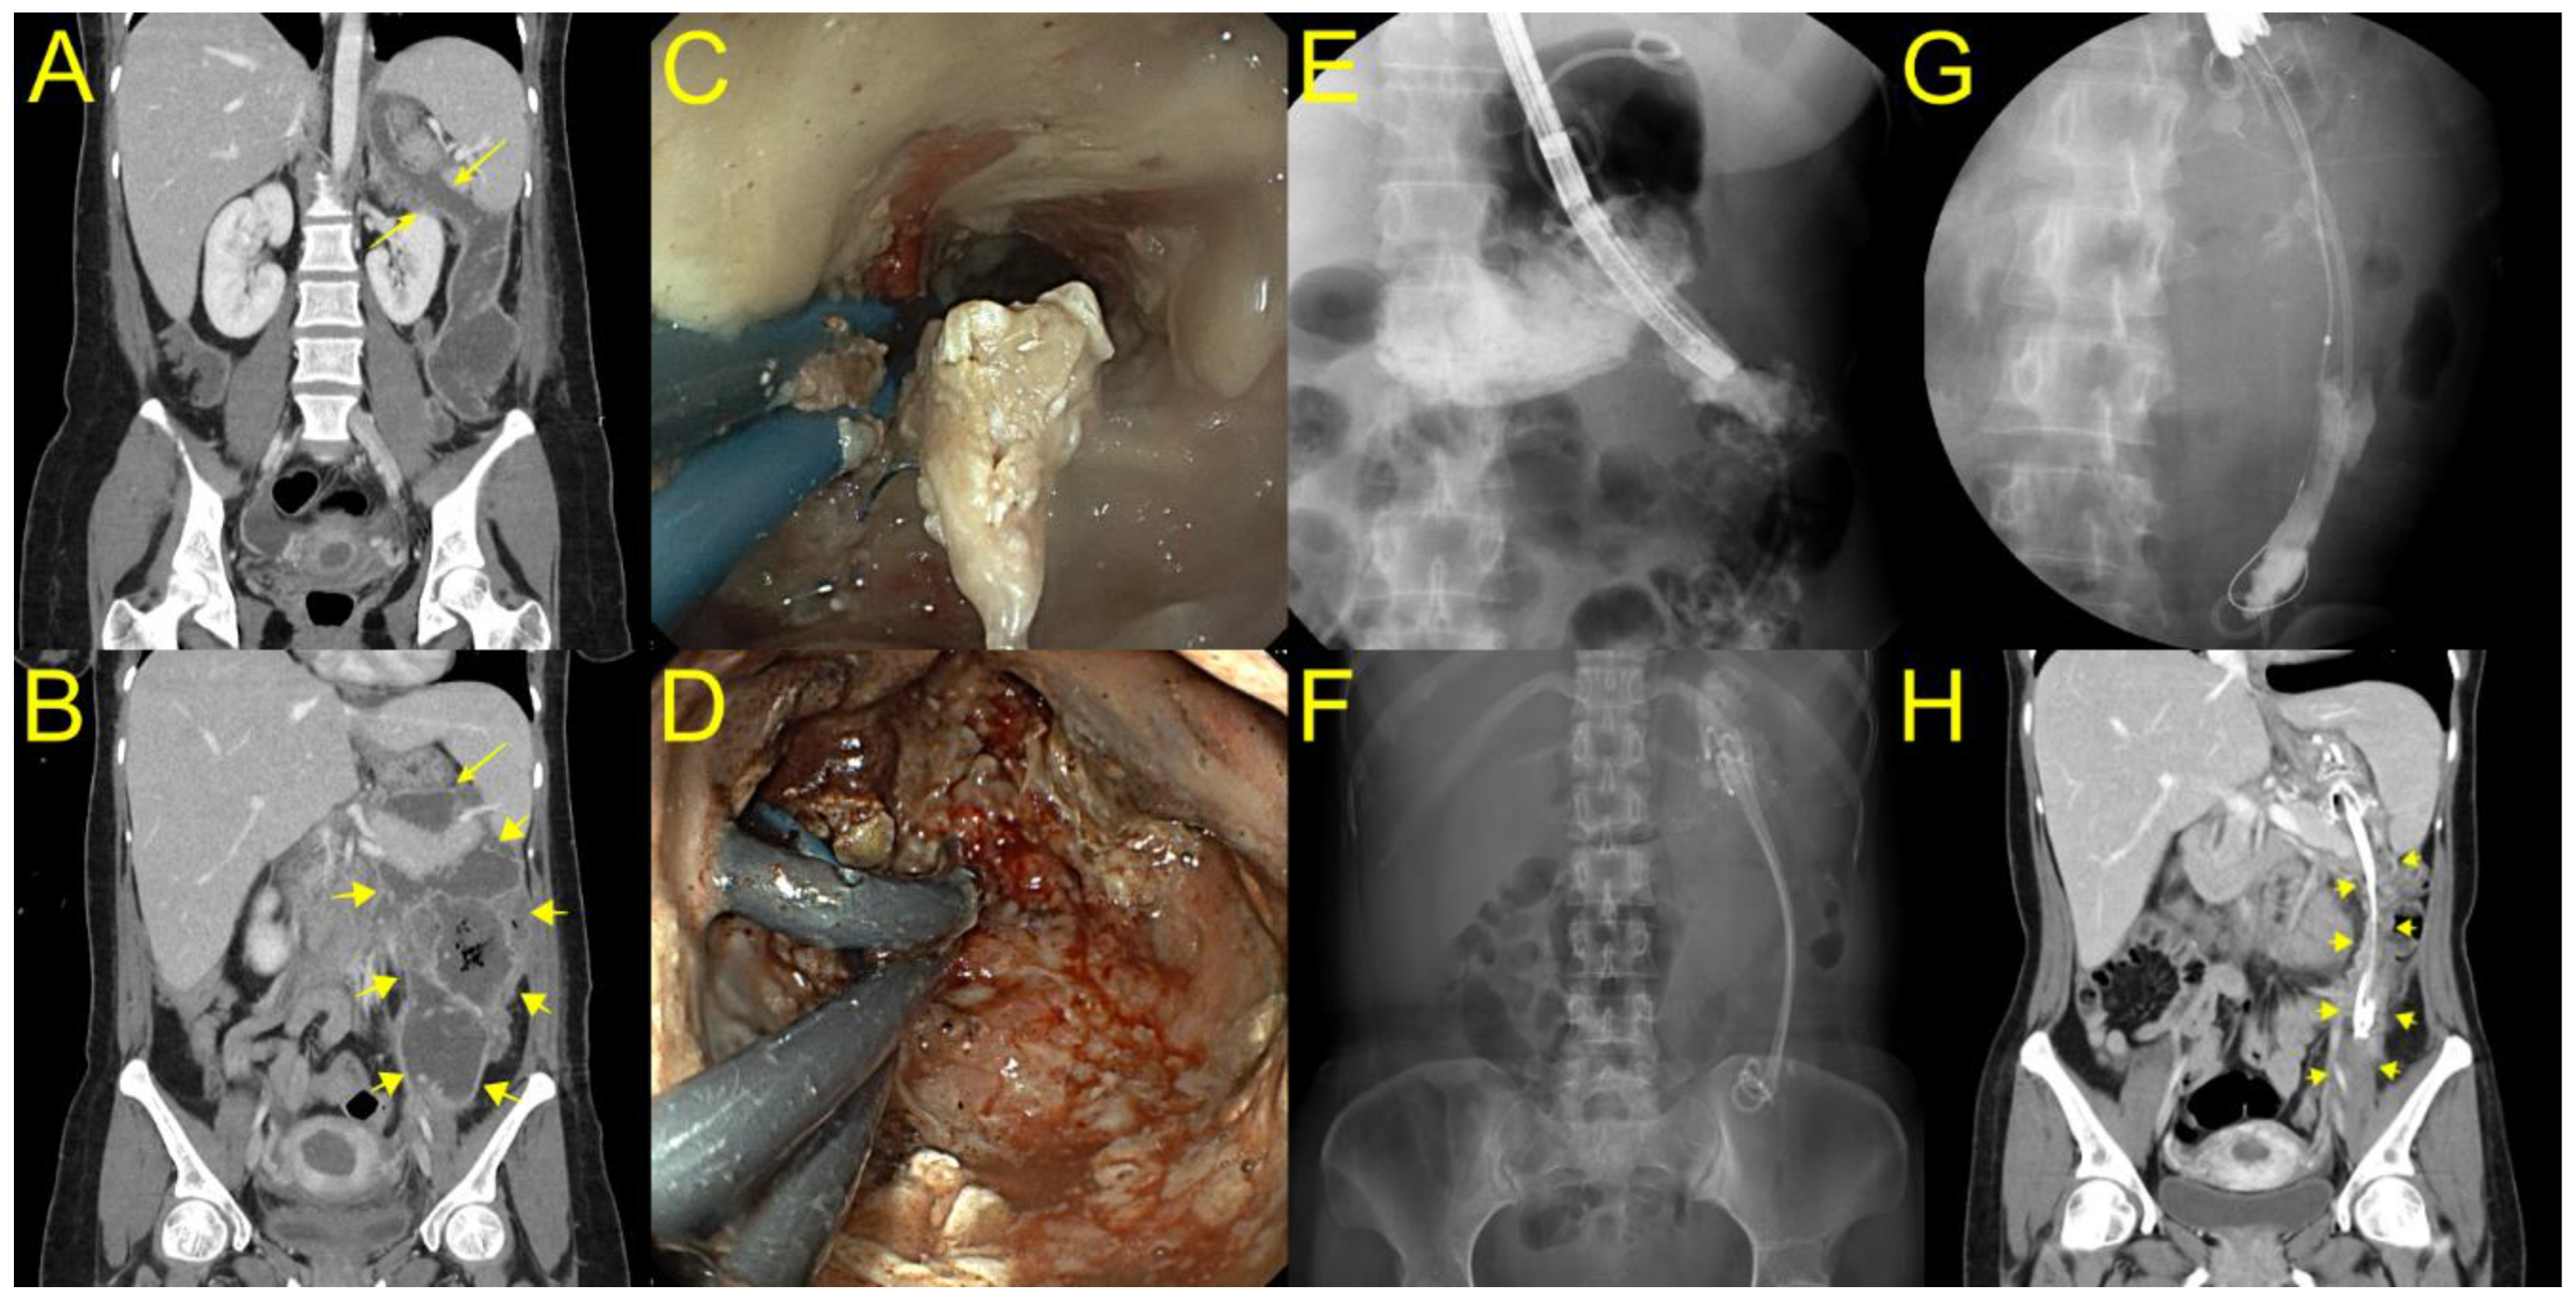

Figure 3. A case of elongated WON extended to the left paracolic gutter. (A,B) Computed tomography showing that an elongated WON (yellow arrow) extended to the left paracolic gutter was concatenated with the stomach. (CE) A gastroscope was inserted into the proximal portion of the cavity through a lumen-apposing metal stent (LAMS), and we found a long narrowing WON endoscopically and radiologically. (F) After DEN, three plastic stents with double pigtail configuration remained in place through LAMS to the deep portion of WON until the next session of DEN. (G) After nine DEN procedures, long plastic stents remained in the deep portion of WON with partial improvement radiologically. (H) After 11 DEN sessions, where the long plastic stents remained in the deep portion of WON, the patient recovered with complete WON resolution (yellow arrow).